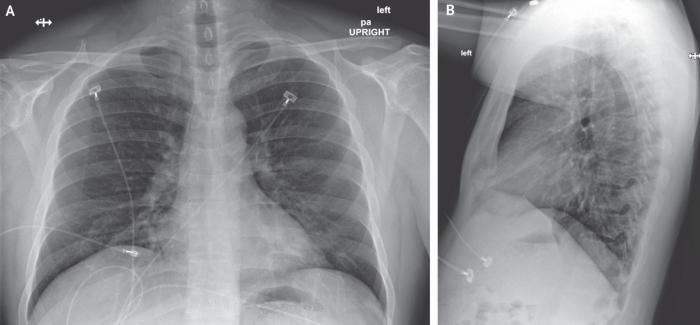

但是,住院第5天晚上(患病第9天)进行的第二次胸部X光片检查显示,左肺下叶有肺炎。这些影像学发现与从住院第5天晚上开始的呼吸状态变化相吻合,当时患者在呼吸周围空气时血氧饱和度值降至90%。住院第6天,患者开始接受补充氧气,该氧气由鼻导管以每分钟2升的速度输送。开始使用万古霉素(1750 mg负荷剂量,然后每8小时静脉注射1 g)和头孢吡肟(每8小时静脉注射)治疗。

2020年1月24日(患病第5天,住院第9天)的后前胸X线片。